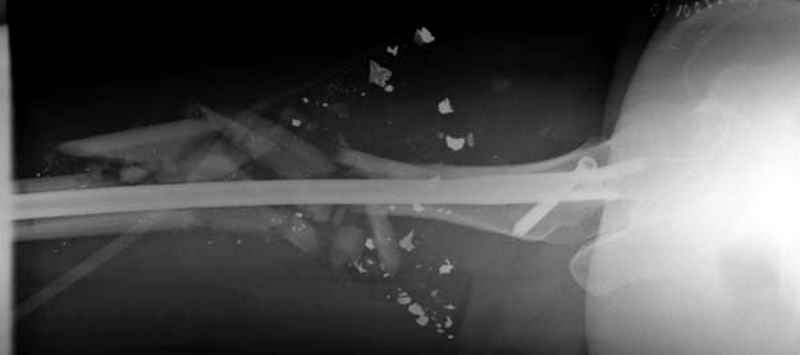

3 такие раны после удаления пули и остатков одежды можно закрыть первично

Вложение не в текстовом формате было извлечено…

Имя     : 3 GSW tibia. postop.jpg

Тип     : image/jpeg

Размер  : 17087 байтов

Описание: отсутствует

Url     : http://weborto.net:8080/pipermail/ortho/attachments/20090726/b21ae3ea/attachment-0013.jpg